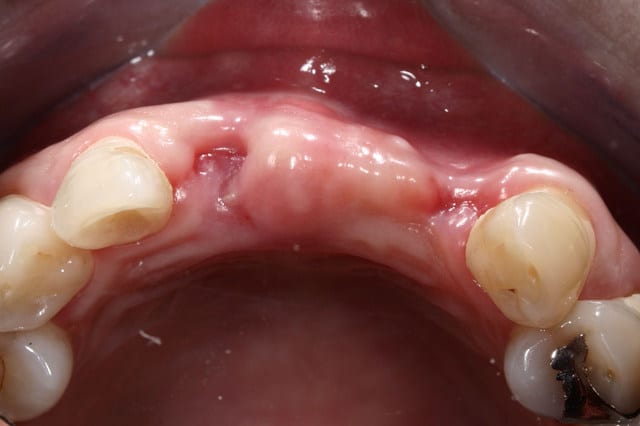

Os de banque

Pose de l'implant la sem passée.